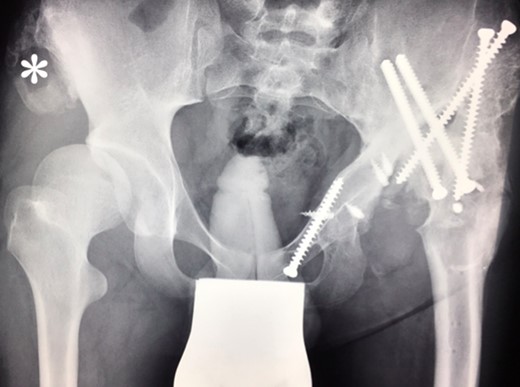

Ten years ago, a 12-year-old male presented to our clinic complaining about limping and massive swelling of the left hip. Figure 1 shows the initial X-ray and the 3D reconstruction of the left hip at first presentation when the femoral head, had already destroyed the lateral edge of the acetabulum like a mortar. Severe pain episodes have apparently not been noticed and a former hip dysplasia was not known. A brief clinical history revealed that the patient presented repeated episodes of finger biting and fevers from 2 to 8 years old. The intelligence level of the patient was at an average. The patient was admitted to a paediatric neurologist and a genetic test. A mutation of the NTRK1 gene was found and the diagnosis of CIPA was established. The right hip initially appeared to be normal and the patient was walking, therefore surgical reconstruction for the left hip was proposed due to massive swelling, inability of normal walking and significant limb length discrepancy. A Tönnis/Kalchschmidt triple pelvic osteotomy with open reduction and a shortening varus derotation osteotomy (VDRO) of the femur was performed (Fig. 2A–B). After 3 months the patient was walking again but another 3 months later the hip dislocated again without severe pain. Although the femoral head was already damaged the hip joint was reconstructed again by open reduction, capsular reconstruction with suture anchors and a trevira tube and a movable external fixator was used to temporary stabilize the joint (Fig. 3). The right hip at this time was still intact and was protected with a pneumatic orthotic device. A few months later in 2009, despite all surgeries, the left hip had entirely lost congruency and the right hip developed subluxation despite conservative treatment (Fig. 4). The patient was still walking so the decision to reconstruct the right hip with open reduction, capsular augmentation with a trevira tube, a triple pelvic osteotomy and VDRO was made (Fig. 5). Few months later this reconstruction failed as well and the hip dislocated without severe pain (Fig. 6).

(2008) Despite reconstruction the femoral head subluxated and rapidly lost congruency. An open reduction and capsular reconstruction with trevira tube, removal of the femoral plate and temporary fixation with an external fixator with movable hip mechanism for flexion of the joint (Orthofix MonoRail) was performed.